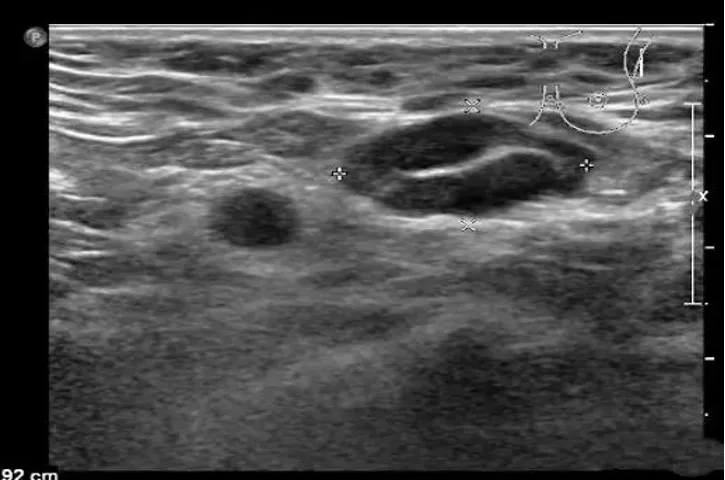

病例:左侧颈部无痛性结节2周,体检颈部可触及数个结节,可活动,无触痛。

超声描述:左侧颈部见数个肿大淋巴结,呈椭圆形,淋巴结之间无融合,大者约28x12mm,皮质增厚,髓质偏移,内部血流信号增多,呈树杈状分布。